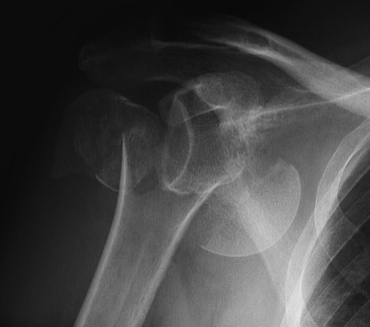

proximal humerus fracture Background ORIF with locking plate Arthroplasty Greater tuberosity fractures Lesser tuberosity fractures / avulsions Book traversal links for Proximal humerus fractures ‹ Pectoralis Major Tears Up Background ›